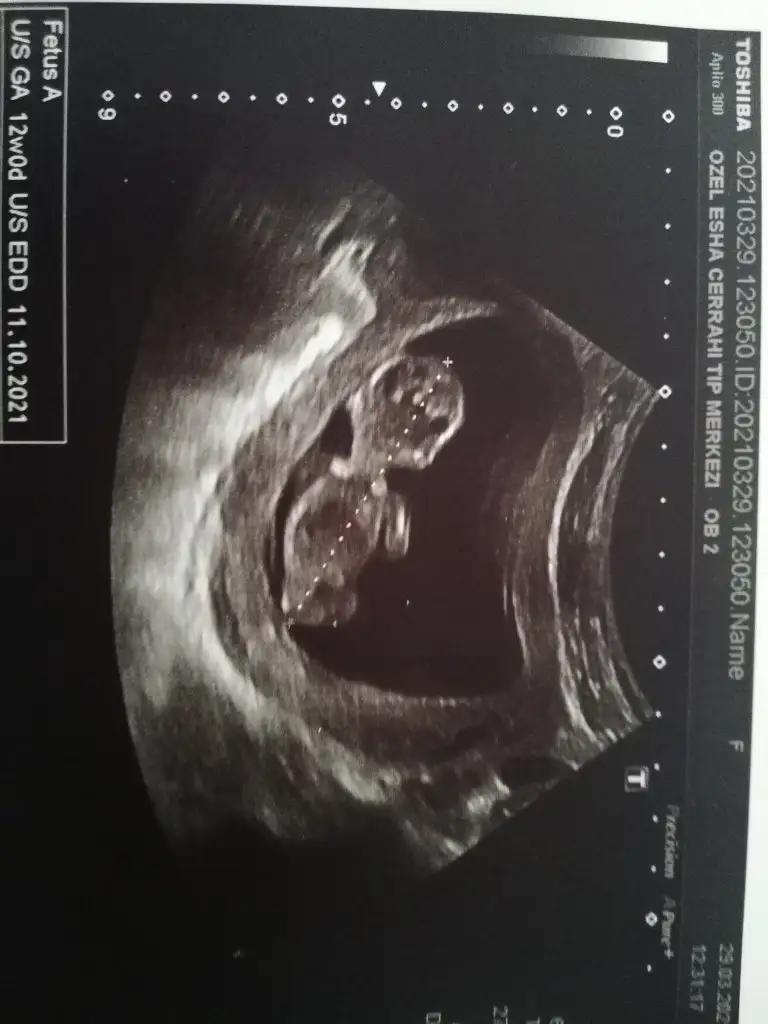

12 haftalıkKac haftalık 11 12 13 haftalar olmalı kız sanki

Dr + getirmiş nubuna görülmüyor tipi kız gibi sanki 11-12 hafta varsa paylaşın